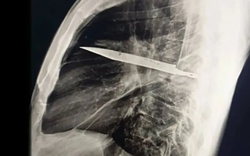

• Đang ăn sữa chua, người phụ nữ nuốt chiếc thìa dài 17cm vào bụng

Đang ăn sữa chua, người phụ nữ nuốt chiếc thìa dài 17cm vào bụng

Một người phụ nữ đã vô tình nuốt phải một chiếc thìa dài 17cm khi con chó của cô nhảy lên đùi trong lúc cô đang ăn sữa chua.